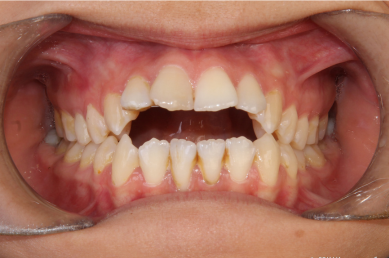

-  اپن بایت، زمانی که دندانهای جلویی فک بالا و پایین هیچ همپوشانی ندارند و بین آنها فاصله است. معمولا بیماران اپن بایت با مشکل گاز گرفتن میوه ها و خوراکیها مواجه هستند.

-  دندان ها روی هم قرار گرفته اند کج و نامرتب هستند. . زمانی رخ می دهد که فضای کافی برای رشد و نمو طبیعی دندان های دائمی وجود نداشته باشد.

اگر هر یک از این علائم را در فرزندتان یا خودتان تشخیص دادید، ممکن است وقت آن رسیده باشد که با یک دندانپزشک ارتودنسی مشورت کنید.

- دندان هایی که به صورت غیر طبیعی به هم می رسند یا اصلا به هم نمی رسند